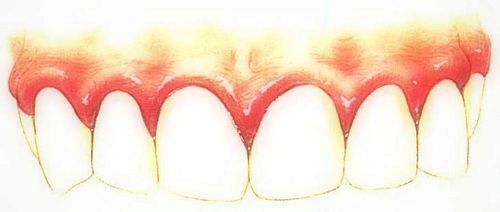

Основні симптоми виникнення запалення ясен

- Кровоточивість ясен.

- Помітне почервоніння.

- Освіта набряклості ясен.